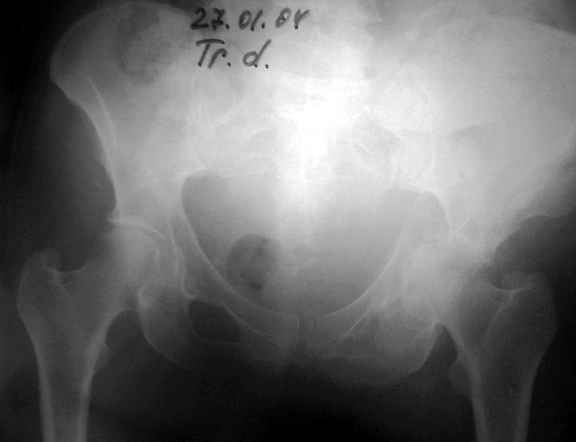

Женя! Класный перелом. Отлично репонируется изнутри таза, но лучше фиксированть сзади. Классический перелом для двустороннего доступа.

27.01.04